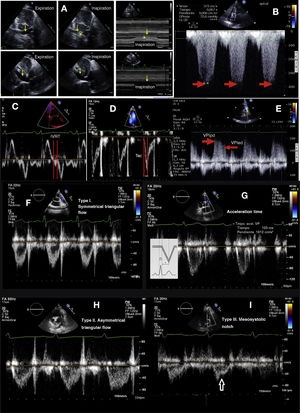

A. Variation of the inferior vena cava. The 2D inspiration and expiration image is shown in M mode. B. Continuous Doppler recording of tricuspid insufficiency. The red arrow indicates tricuspid insufficiency maximum velocity. C. Isovolumetric relaxation time (IRT). D. Pulmonary artery acceleration time (Tac). E. Pulsed Doppler recording of pulmonary insufficiency. The arrows indicate the protodiastolic maximum velocity of the pulmonary insufficiency flow (VPIed) and the end-diastolic maximum velocity of the pulmonary insufficiency flow (VPIed). F. Normal type I pulmonary artery flow with symmetrical ascent and descent. G. Type I pulmonary artery flow with symmetrical triangular follow, normal flow. H. Type II pulmonary artery flow with asymmetrical triangular follow, suggestive of increased pulmonary pressure. I. Type III pulmonary artery flow with an arrow indicating the mesosystolic notch due to early closure of the pulmonary valve.

Collapsibility index (CI) of the inferior vena cava (IVC). The IVC is measured in the subcostal plane at 1–2 cm from its access to the RA, behind the hepatic vein, with the patient in the supine position and at the end of expiration. Formula: CI = [Dmax IVC - Dmin IVC]/Dmax IVC). In critically ill patients there are situations where dilatation of the IVC without respiratory collapse does not predict the response to crystalloid administration45 (Fig. 4A).

Systolic pulmonary artery pressure (PAPs)Color Doppler is used to record TI, placing the continuous wave (CW) Doppler cursor with good alignment to calculate the maximum velocity of TI (VmaxTI), which is equivalent to the pressure gradient between the RA and RV. In situations of massive TI, the formula is not applicable, since the inertial component is not negligible. PAPs = 4 x VmaxTI2 + RAP (Fig. 4B).

Pulmonary artery acceleration time (Tac), which is the interval from the start of ejection of the RV to the peak flow velocity through the pulmonary valve (Fig. 4D–G). The 60/60 sign is associated to Tac < 60 with a tricuspid systolic gradient > 30, but < 60 mmHg.

Calculation is made of the peak velocity of PI in end-diastole (VPIed) in the short parasternal axis plane at the large vessel level (Fig. 4E). This method is imprecise in the presence of massive TI.

We can also evaluate PVR in a semi-quantitative manner observing the presence of “notches” in the PW spectrum of the flow velocity in the right ventricle outflow tract (Fig. 4F–H). A mesosystolic notch is indicative of severe PHT (Fig. 4I).